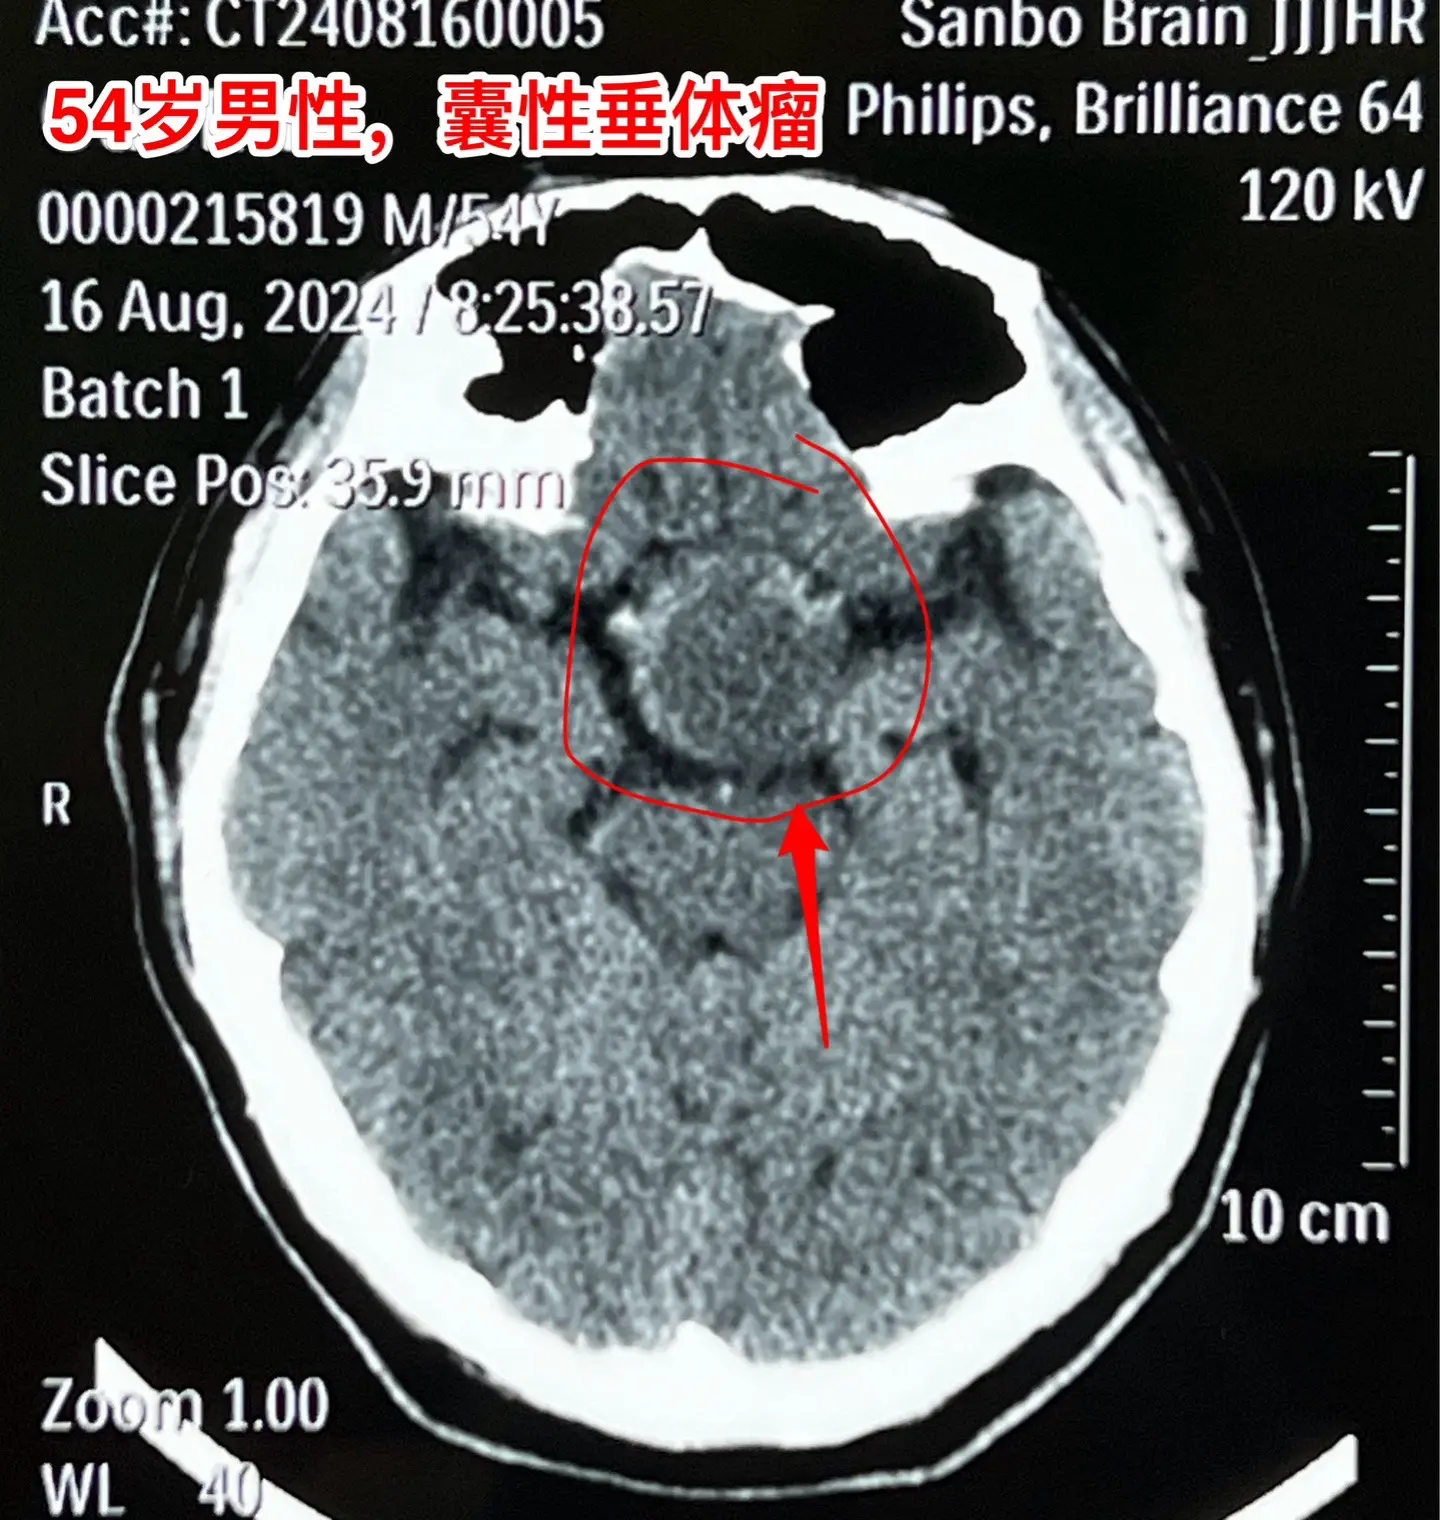

中元节是不是不适合作手术?昨天8月18号是中元节,我们科在上周提前安排在这一天作一台垂体瘤手术,那个时候我还没有想到这一天是中元节。 患者的女儿提到这日子不太好,是中元节,我才意识到的确不太合适。我就说,不行就在8月19日晚上作。这个女儿又说不行,因为8.19是病人的生日!我说如果这样的话只能往后推了,因为前面的手术都排满了。 患者女儿和家人商量了之后还是决定在8.18日作手术,因为之前患者为了排查冠心病,已经耽误了好几天时间,为了能缩短住院时间,他们只好选择8.18这个日子。 患者家属下定决心了,我心里却担心起来了!心里有隐隐的不安和恐惧,但是也不敢告诉病人。 昨天的手术很顺利,手术后我一直在医院等病人完全清醒了,作完了头部CT,结果很满意。在确保病人平安无事了我才敢离开医院。唯恐出现意外! 今天查看病人,病人精神好,自诉视野缺损情况有改善。我彻底放下心来了!